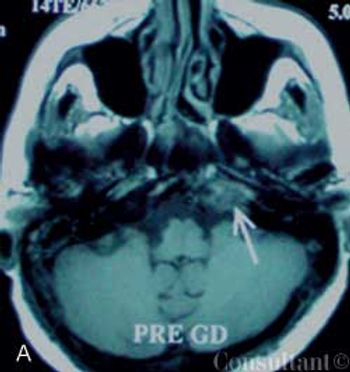

A 75-year-old woman with a bioprosthetic aortic valve, who had undergone surgical repair of an aortic root aneurysm 9 months earlier was hospitalized with fever, headache, and altered mental status of 1-day's duration.